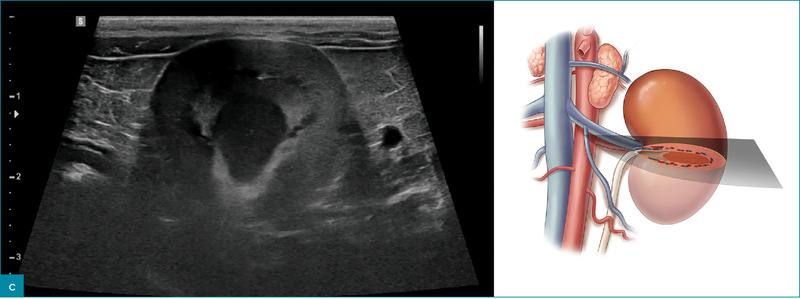

Ryc. 1. Obrazy ultrasonograficzne prawidłowej nerki kota w projekcji: a) strzałkowej, b) dogrzbietowej oraz c) poprzecznej. Towarzyszące ilustracje przedstawiają przebieg płaszczyzn obrazowania.